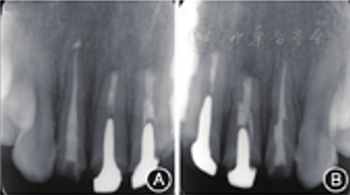

见图8,图9,图10,图11。分别于术后3、6个月时复查根尖X线片,8个月时复查锥形束CT并分别进行临床检查。复查结果显示根尖病变已愈合,根尖无明显低密度影。临床检查叩诊正常,无松动,牙龈位置无明显变化。

图8 术后3个月复查患者根尖X线片 A:根尖病变明显缩小;B:根尖病变明显缩小